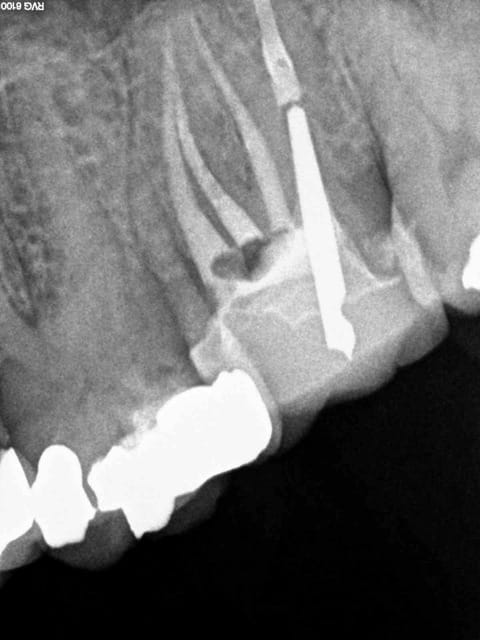

bon attend je vais chercher mes lunettes ,par ce que je ne vois rien de si mediocre au niveau endo . de quelle radio parles tu ? on parle bien de la 2 eme au milieu ?

La plus claire pour moi est la troisième tout à droite, la gutta ne disparaissant pas j'en déduis que l'obturaton sur la deuxième est constituée essentiellement, sinon exclusivement de ciment, je te fais la même en 10 minutes, tire nerfs lentulo pâte, un cône accessoire histoire de en distal.

Je suppose aussi qu'il s'agit de la radio preop du dentiste suivant et qu'il n'a pas encore déposé.

C'est quand-même dommage d'arriver à l'apex et d'obturer avec un matériau résorbable, non? Objectivement cette endo à trois ans est pourrie. La post-op ok il y a du matériau radio opaque à l'apex, mais celle avec la couronne... J'ai le souvenir d'un étudiant qui à la fac fabriquait le ciment d'obturation en mettant de l'eau distillée au lieu de l'eugénol. Pas cool.

Remarquons aussi qu'il manque la 47... qu'en est-il de la (sur)charge occlusale?

question con surement mais en distal il y a avait un cone de gutta

il est passé ou sur l'image N°3

ca disparait pas ce genre de truc....normalement